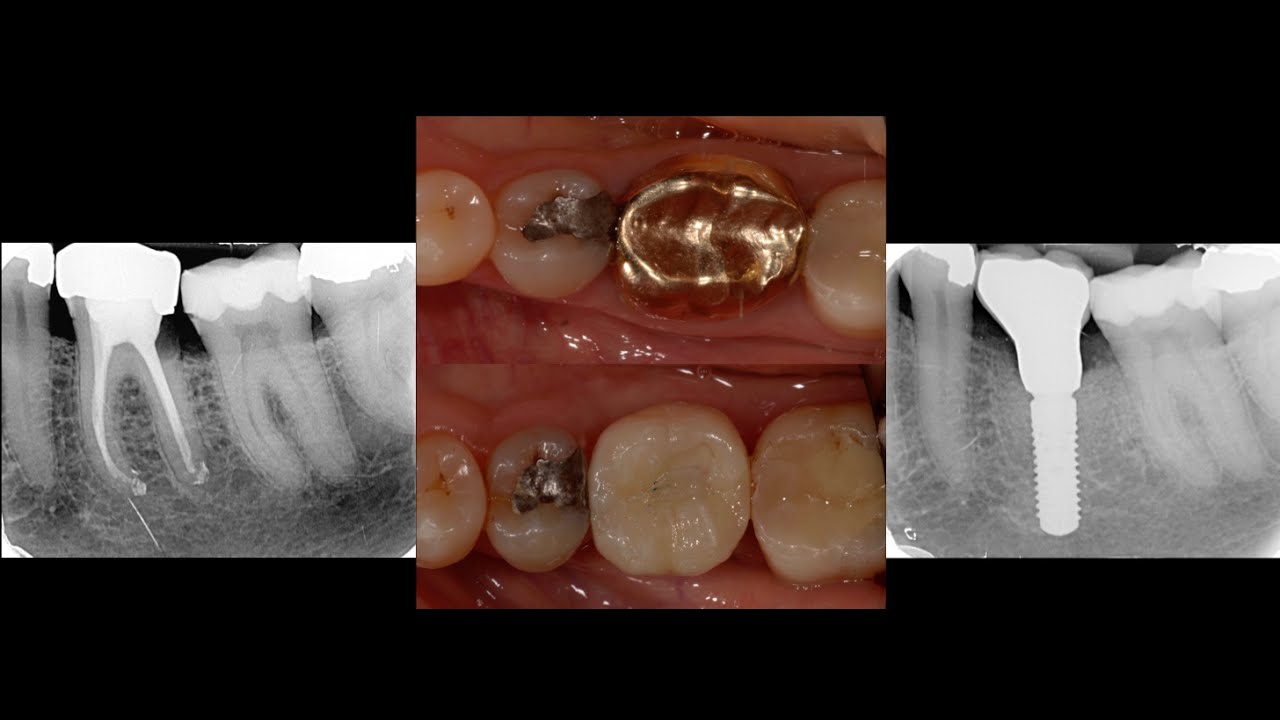

Immediate Placement of Dental Implants in Molar Extraction Sockets An Dental Surgery Molar Extraction larger wounds (i.e. an oral surgeon, not a dentist, may extract a tooth when the situation is more complicated. Third molar removal, especially in the case of impaction, may require a more complicated surgical extraction. after a tooth extraction, proper aftercare is vital, as it helps promote clotting and protect the extraction site during the healing process.. Dental Surgery Molar Extraction.